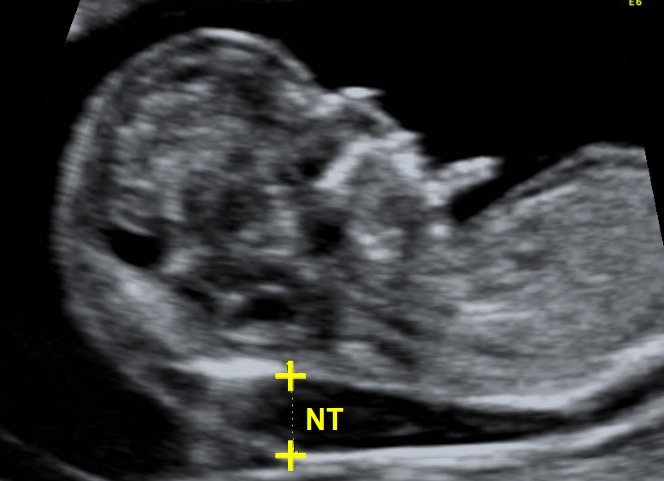

Wat Is Een Nekplooi. Zoals eerder aangehaald is de nekplooi een translucent gebied te zien op echografie die normaal verdwijnt na 14 weken zwangerschap. Toch willen wij het zeker weten. Wat is de nekplooi. Bij een zwangerschapsduur tussen 11 en 14 weken is bij elke foetus een klein schilletje vocht onder de huid in de nek aanwezig.

De specialist in het radboud ziekenhuis zei dat het echt heel normaal is dat de nekplooi vóór 11 weken en 3 dagen nog dikker kan zijn omdat de lymfe zich dan ontwikkelen. Mischien heeft de specialiste een ander reden voor verder onderzoek denk dat je dat best eens kan vragen. In het nekje is dan vaak een beetje vocht aanwezig deze vochtophoping is gewoonlijk niet meer dan 3 mm dik. Zoals eerder aangehaald is de nekplooi een translucent gebied te zien op echografie die normaal verdwijnt na 14 weken zwangerschap. De breedte van dit schilletje wordt gemeten tot op 01 mm nauwkeurig. De nekplooi is een dun vochtlaagje onder de huid in de nek.